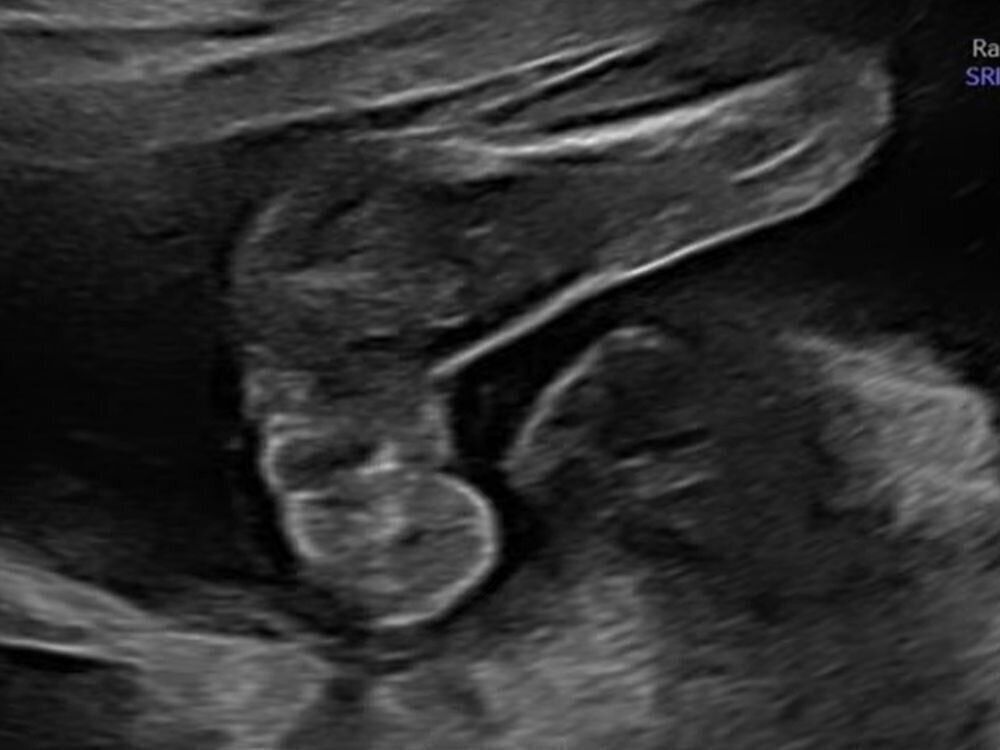

「幸い、待てど暮らせどつわりもなくて、私の体調もよかったんですが、双子だから通常よりリスクが高いということで、妊娠19週のころに、妊娠中期のスクリーニングエコーという、より詳しい長い時間をかけてしっかり診ていくエコー検査を、医師の勧めもあって受けることになりました。

それまでの健診で受けたエコー検査では、2人とも大きさも週数どおりで、何も指摘されていなかったですね。だから、まだわかっていなかった2人の性別が、スクリーニングエコーで詳しく検査したら、きっとわかるんやろうなぁっていうくらいの気持ちで受けたんです」(あかりさん)

そして、そのエコー検査で、おなかの赤ちゃんに右足欠損という障害があることがわかったのです。

検査は、第1子となる、子宮口に近い位置にいた赤ちゃんの検査から。心臓にちゃんと4つの部屋があるかなど、臓器1つずつの確認や、四肢が形成されているかどうかなどを2時間くらいかけて、すごく詳しく診てもらったそうです。

「第1子となるゆーちゃんの検査を先にやって、『うん、問題ないね』と言われて、次に第2子となるきーちゃんのエコーを見ていたんです。そのときにはもう2人の性別もわかっていて、先生と世間話をしながら、検査を受けていたんですね。

そしたら、最後に先生の手が止まって『ちょっとここ、詳しく診たいので…』と言ってほかの先生を呼んで、2人でお話しされながらエコーを見ていらしたんです。その雰囲気から、私も『なんかあったんやろうな』と感じました。

しばらくして、医師に『お母さん、驚くかもしれないけれど、第2子の子の右足が見えません』と言われました。さらに、右足がないことで、ほかの四肢にも障害がある可能性があると言われ、ほかの手足についてもさらに詳しく診てもらい、左足については先天性内反足(せんてんせいないはんそく)※であることがわかりました。